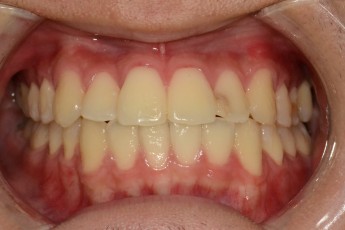

BEFORE & AFTER

- 돌출입교정